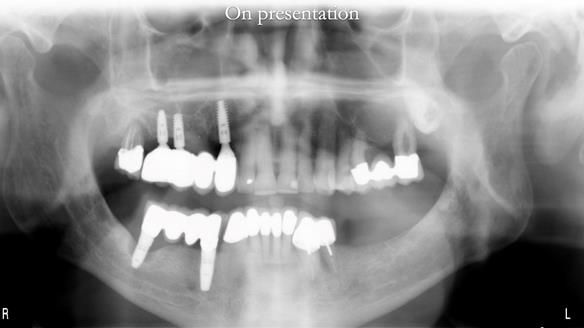

The upper jaw

In the upper arch:

- a failing upper left tooth supporting a bridge was removed

- an implant-supported bridge on the upper right was dismantled

A metal-based upper RPD was made,

with metal backings incorporated to future-proof the design

should further teeth fail.

In 2016, Ken developed pain from tooth 32.

Endodontics was not possible.

The root was resected.

The tooth was already linked to 41 and 42,

and we were able to retain it

without compromising denture stability or retention.

In 2022, tooth 43 fractured.

An artificial tooth was added to the RPD

by welding a cobalt–chrome tag to the bar

and adding the tooth.

The denture continued to function extremely well.